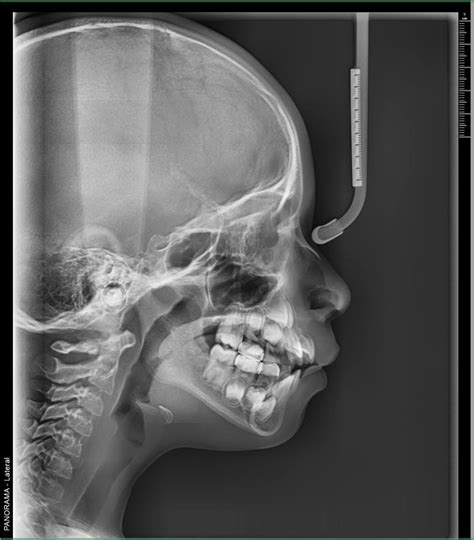

Radiografías Extraorales

Las radiografías extraorales son técnicas de diagnóstico por imagen en odontología en las que el sensor o película radiográfica se coloca fuera de la boca del paciente. Es fundamental para los análisis cefalométricos que determinan la posición y alineación de los dientes, así como la relación entre los maxilares y el cráneo.

La radiología dental ha avanzado significativamente en las últimas décadas, gracias a la adopción de tecnologías innovadoras que han transformado la obtención, procesamiento y análisis de imágenes. En la práctica odontológica moderna, la radiografía dental se ha convertido en una herramienta indispensable. Estas imágenes permiten a los odontólogos ver lo que a simple vista es imposible detectar, proporcionando una visión detallada de la estructura interna de los dientes, huesos y tejidos circundantes. Esto es crucial para el diagnóstico preciso de enfermedades y condiciones dentales, así como para la planificación de tratamientos efectivos. Desde la detección temprana de caries hasta la evaluación de problemas periodontales y la planificación de tratamientos de ortodoncia, las radiografías son fundamentales para ofrecer una atención de calidad a los pacientes.

Destacan los sistemas digitales, que permiten obtener imágenes de alta resolución al instante, y las técnicas tridimensionales como la tomografía computarizada de haz cónico, que brindan una visión completa de las estructuras orales y maxilofaciales. La integración de software especializado y herramientas de inteligencia artificial ha facilitado la detección automática de patologías y una planificación más precisa de tratamientos complejos, como implantes y ortodoncia.